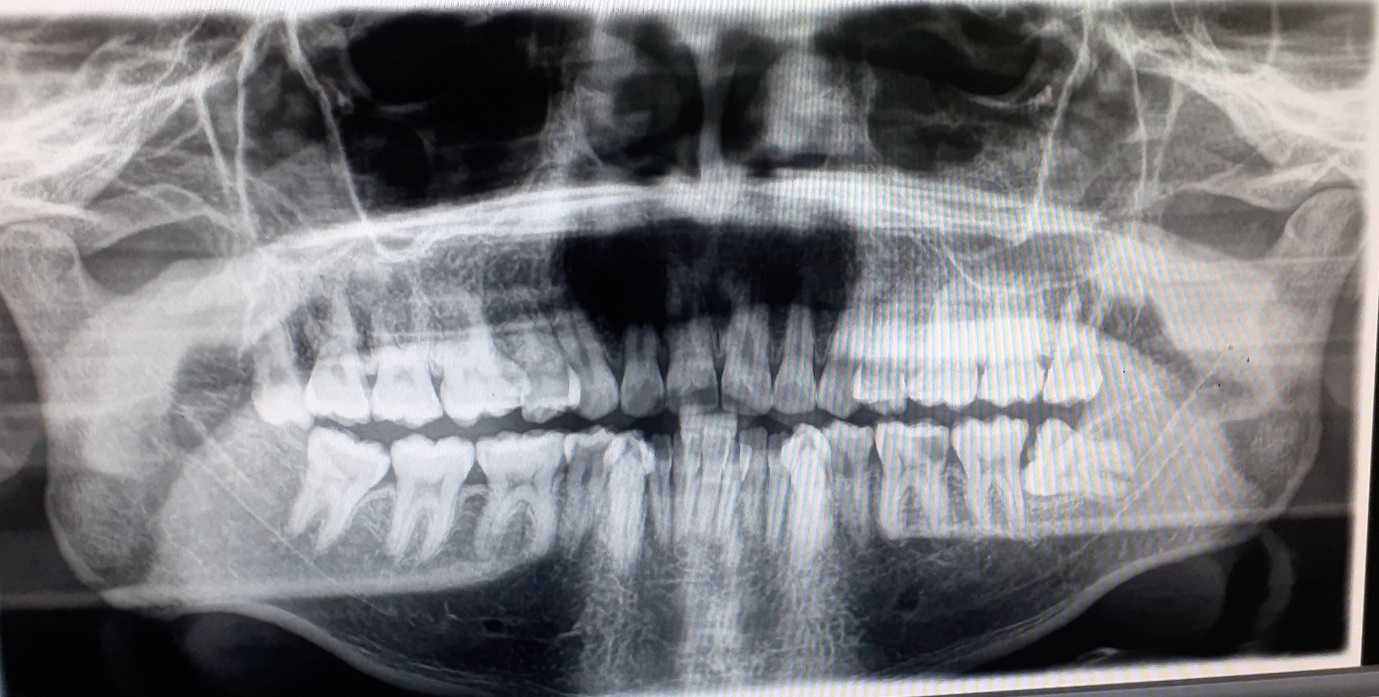

Our experienced team carefully evaluates each case through dental X-rays, studying the root shape and position to plan the optimal approach.

A dental x-ray to study the root shape and position is done so as to guide the clinician. This helps to avoid damage of these nerves while doing the surgical removal of an impacted tooth.